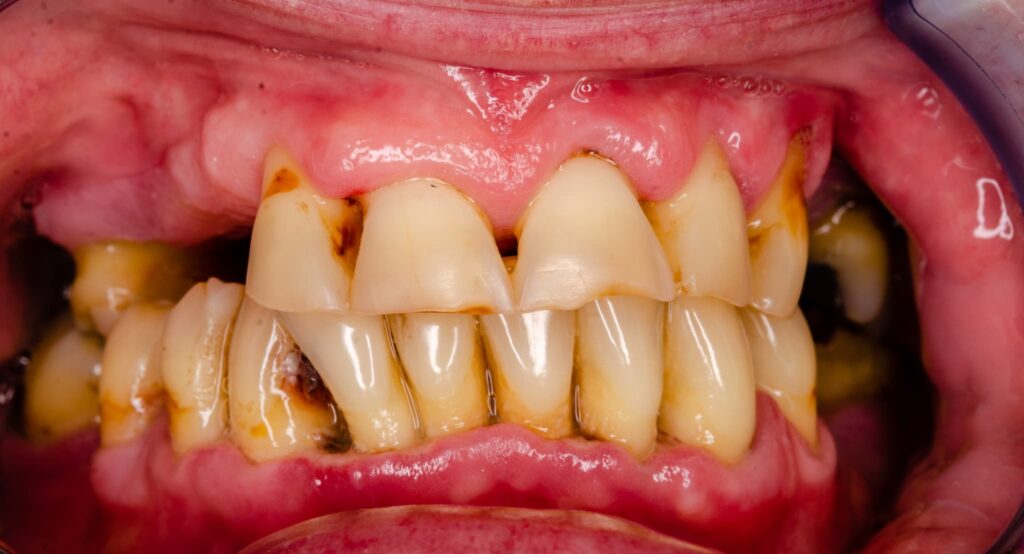

歯周病が進行してしまった口腔内

歯周病はその進行度合いに応じていくつかの段階に分類されます。進行段階によって、症状の現れ方や治療法が異なるため、事前によく理解しておくことが重要です。

重度の歯周炎

重度の歯周炎では、歯を支える骨が大きく破壊され、歯がぐらつくようになります。この段階にまで進行すると、歯茎が腫れるだけでなく、膿が出たり強い口臭が発生したりなど、症状が顕著になります。最悪の場合には、抜歯が必要になることもあるでしょう。